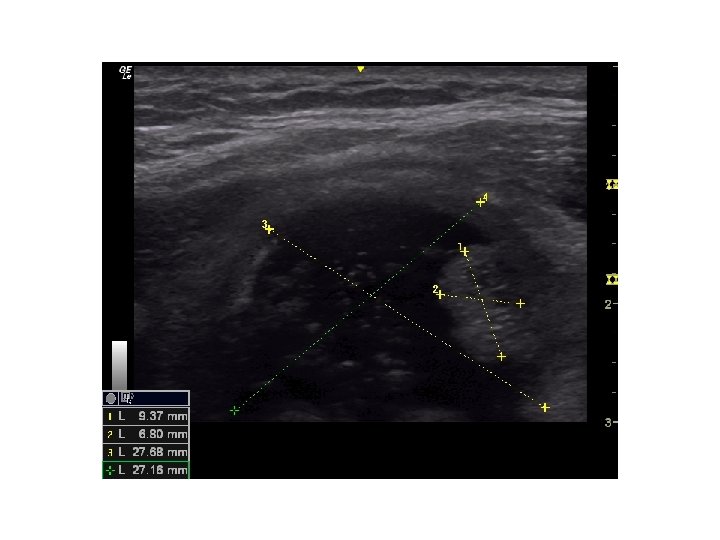

• Tiroid USG • Klinik olarak veya • diğer görüntüleme yöntemlerinde saptanan nodülün tanısının konması için gerçekleştirilir. • USG nodülün – – – – – Boyutu Lokalizasyonu İçeriği Kenar düzeni, Kalsifikasyon varlığı, Ekojenite, Vaskülarite, Şeklinin ve Lenf nodüllerinin değerlendirilmesi için kullanılır.

Sonografik Özellikler, Tahmini Malignite Riski ve İİAB Önerileri Sonografik patern US özellikleri Tahmini Biyopsi için önerilen çap malignite riski >%70 -90 >1 cm Yüksek risk Solid hipoekoik nodül veya solid hipoekoik komponenti bulunan parsiyel kistik nodül: düzensiz sınırlar (infiltratif, mikrolobüle, dikensi), mikrokalsifikasyonlar, boyun enden daha uzun olması, çevrede hipoekoik yumuşak doku komponenti bulunan bozulmuş çevresel kalsifikasyon alanları, tiroid dışına uzanımın kanıtı Orta risk Mikrokalsifikasyon, tiroid dışı uzanım ve uzunlamasına şekil içermeyen düzgün sınırlı hipoekoik solid nodüller %10 -20 >1 cm Düşük risk Mikrokalsifikasyon, tiroid dışı uzanım ve uzunlamasına şekil içermeyen düzgün sınırlı izoekoik/hiperekoik solid nodül veya kenarında uniform solid alanlar içeren kısmen kistik nodül %5 -10 >1. 5 cm Çok düşük risk Ultrasonografik olarak yüksek, orta veya düşük risk tanımlamaları içinde yer almayan spongioform veya kısmen kistik nodüller <%3 >2 cm yapılabilir İİAB yapılmadan izlem de makul bir seçenektir Benign Pür kistik nodüller (Solid komponent yok) <%1 Biyopsi gereksiz( Kist aspirasyonu, semptomlara yönelik veya kozmetik amaçlı planlanabilir. )